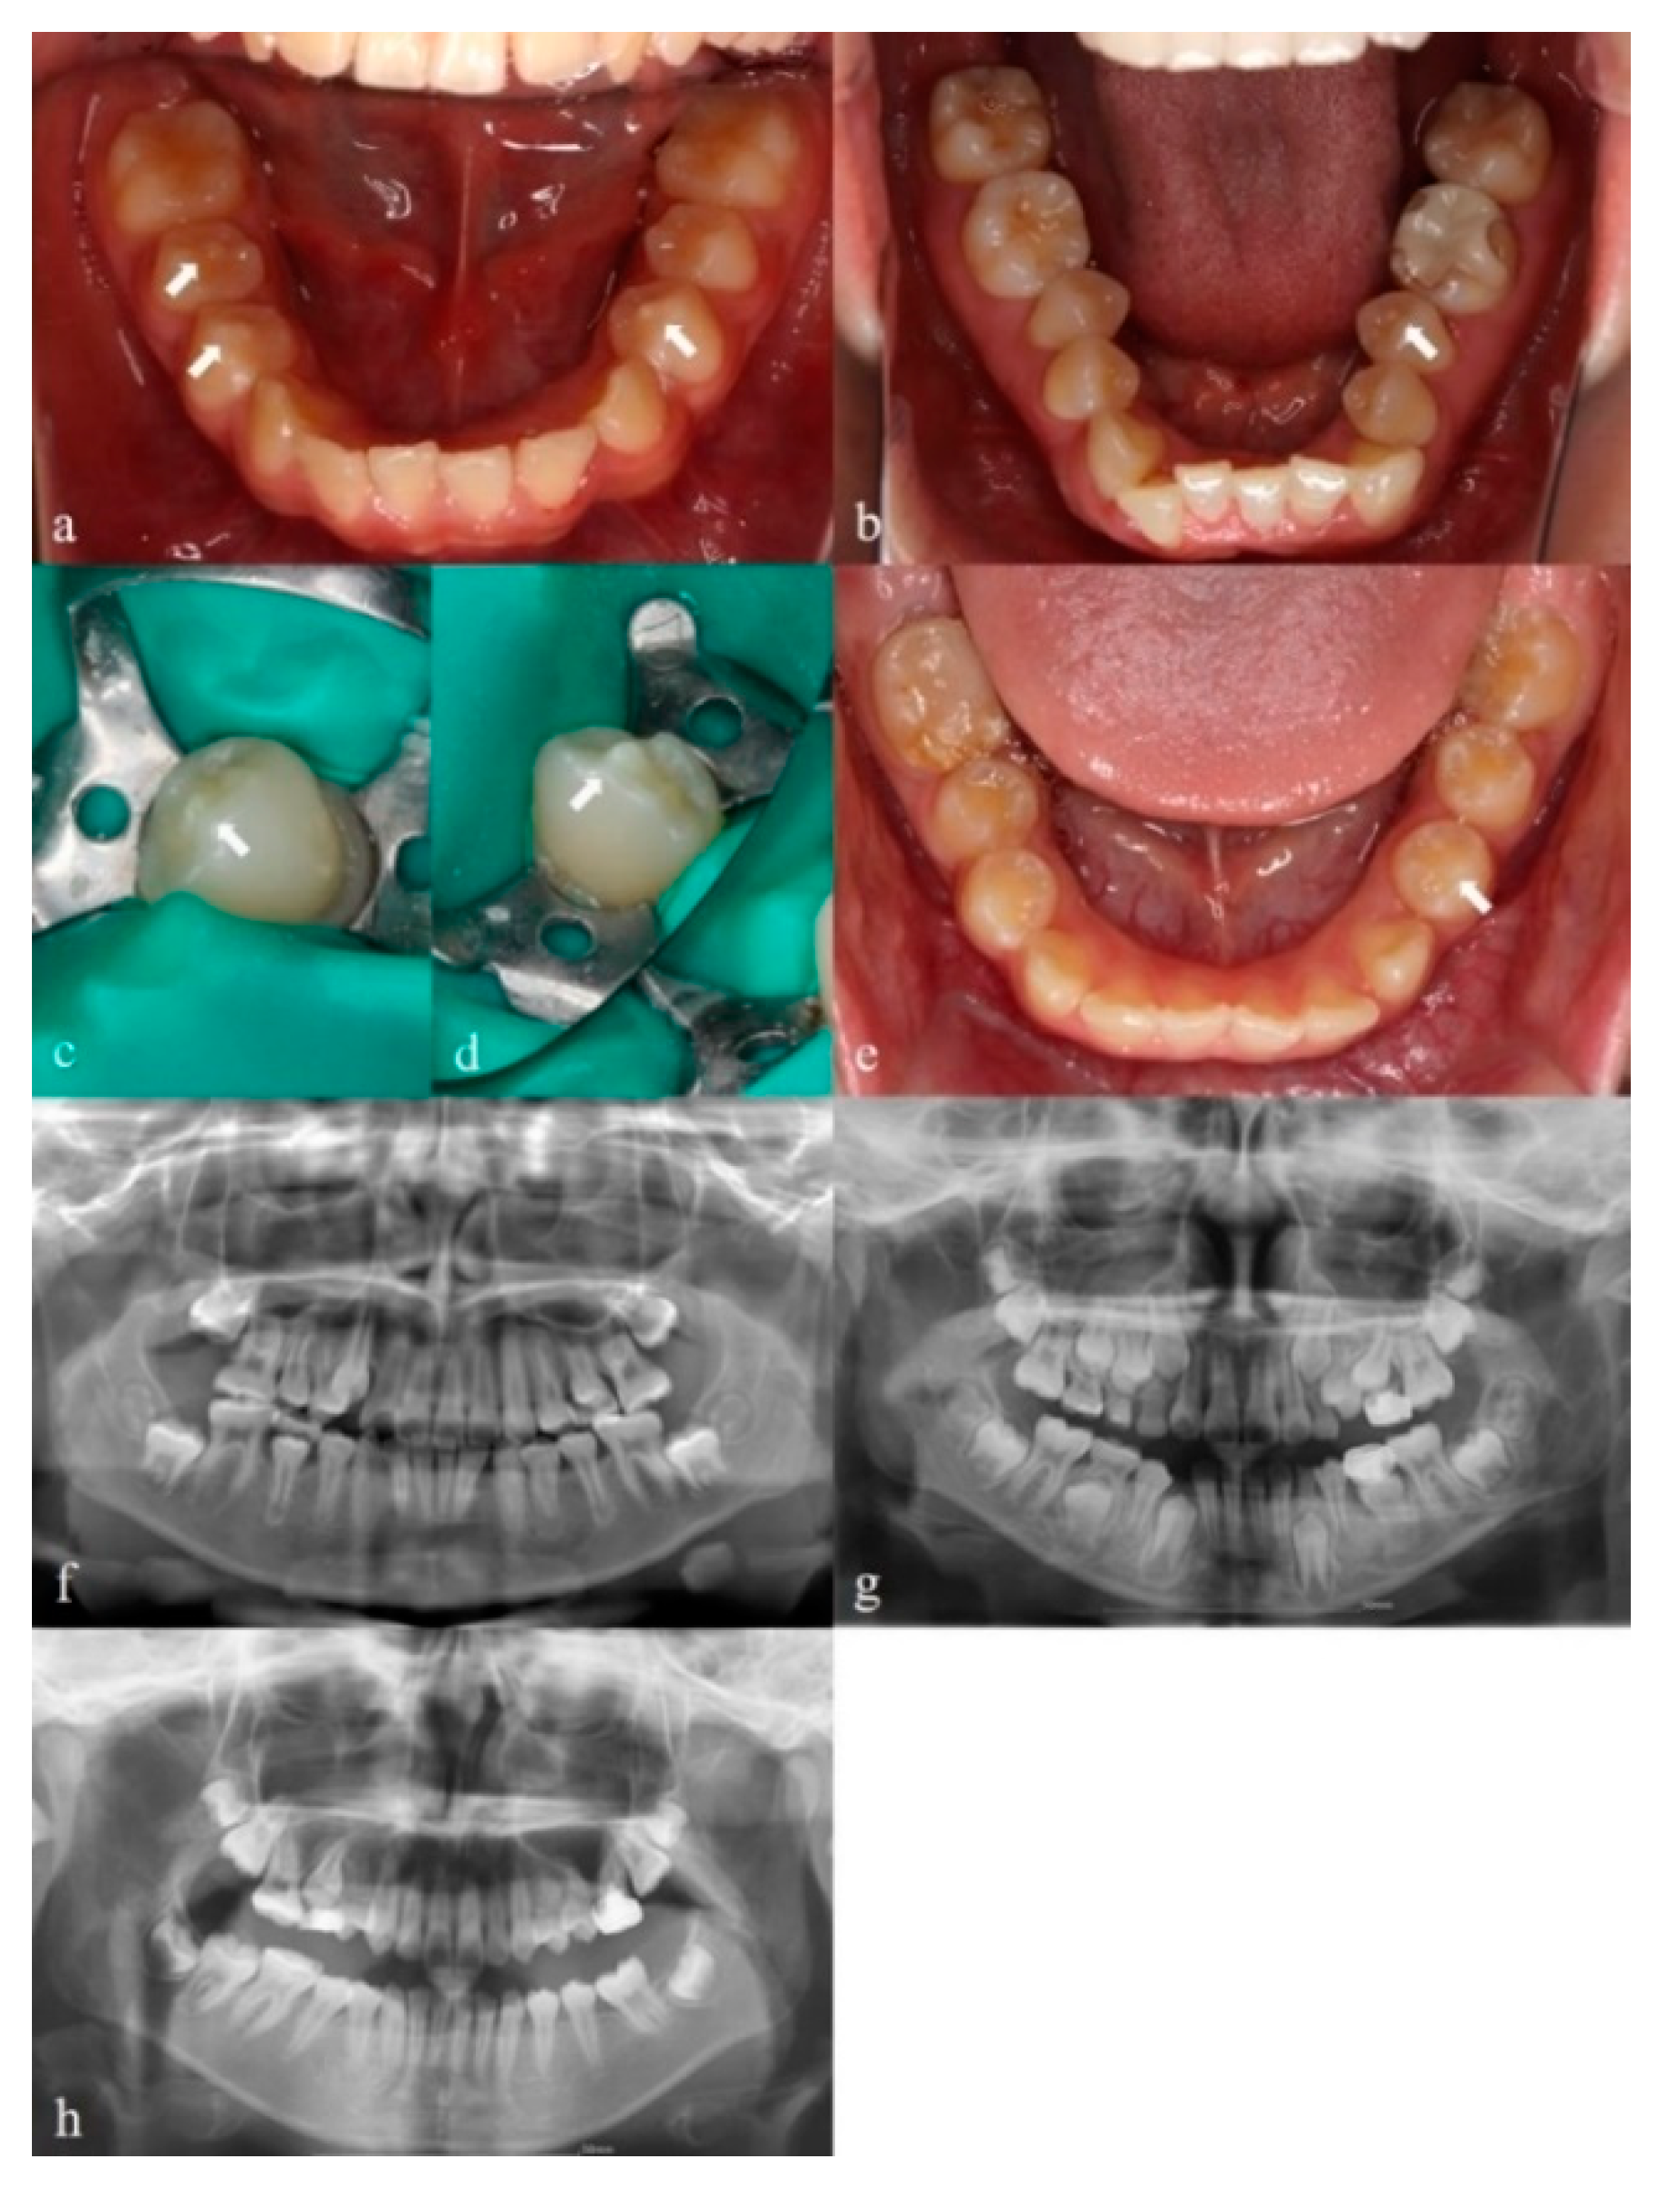

3.1. Clinical Findings

| Subject * | Sex | Dental Arch | Dens Evaginatus | Inclusion Type |

|---|---|---|---|---|

| A-1 | Female | Lower | Left and right first premolar, right second premolar | Bilateral |

| A-2 | Female | Lower | Left second premolar | Monolateral |

| B-1 | Male | Lower | Left and right first premolar | Bilateral |

| B-2 | Female | Lower | Left first premolar | Monolateral |

| B-3 | Female | - | - | - |